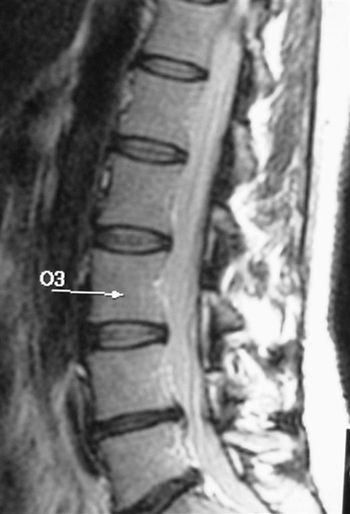

Results of a study by Greek researchers suggest that percutaneous disc decompression, a newly developed outpatient procedure for herniated vertebral discs, has better long-term effects than conservative therapy. They released findings Wednesday at the 2009 RSNA meeting.